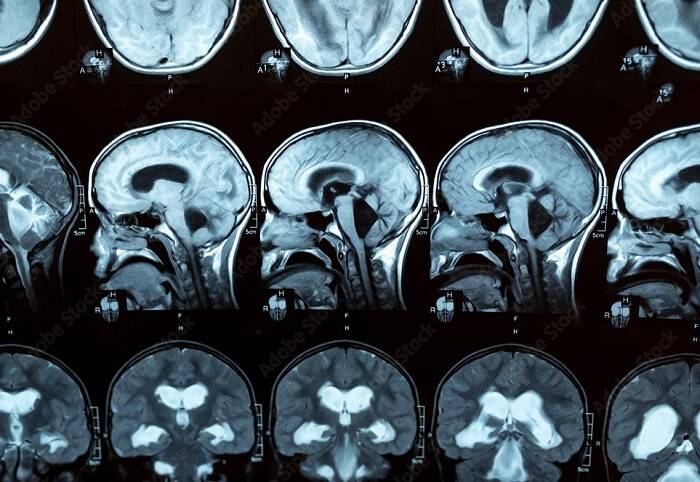

استفاده از شنت مغزی در درمان هیدروسفالی Hydrocephaly در پزشکی دارای سابقه بیش از 50 ساله می باشد. کارکرد اصلی مایع مغزی نخاعی نقشی حیاتی در سیستم خودتنظیم مغز در جریان خون مغزی را در بدن ایفا می کند. استفاده از دستگاه شنت مغزی که طی یه عمل جراحی تحت بیهوشی عمومی در مغز جایگذاری می شود باعث انتقال مایع مغزی نخاعی به دیگر بخش های بدن (عموما شکم) که قابلیت جذب را دارا می باشند می شود.

استفاده از شنت مغری مناسب این امکان را به بیمار می دهد تا زندگی بهتری داشته باشد و این آرامش را به خانواده وی برگرداننده که جایگذاری و استفاده از شانت یک روش درمانی متداول و مرسوم برای درمان بیماران هیدروسفال می باشد. اگر بیماری هیدروسفالی به موقع درمان شود، مشکل جدی را برای انسان ایجاد نمیکند، در غیر این صورت به بافت مغزی آسیب وارد کرده و منجر به اختلالات روانی یا فیزیولوژیکی میشود. یکی از راههای درمان این بیماری، خارج کردن مایع اضافی از مغز است که این کار با قرار دادن دستگاه شانت در زیر پوست سر می باشد.

دارای دریچههای ویژهای هستند که میتوان آنها را تنظیم کرد تا مایع کمتر یا بیشتر تخلیه شود. دارای قابلیت تنظیم جهت افزایش و یا کاهش فشار داخل جمجمه می باشد. این نوع شانتها قابلیت CT و MRI را نیز دارند ولی در اثر MRI ممکن است تنظیمات آن عوض شود که با مراجعه به پزشک دوباره تنظیمات قبلی بر روی آن اعمال می گردد.